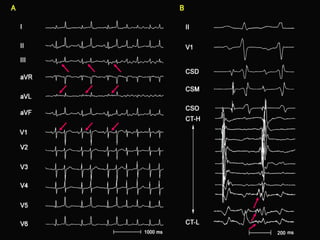

Hypothesis: Wavefront Propagation during AT

QS pattern                   Multi-component

pattern

Wrap-                        Wrap-

around                       around

Effect (-)                   Effect (+)

Surrounding tissue           Surrounding tissue with

without anisotropic          anisotropic conduction

conduction